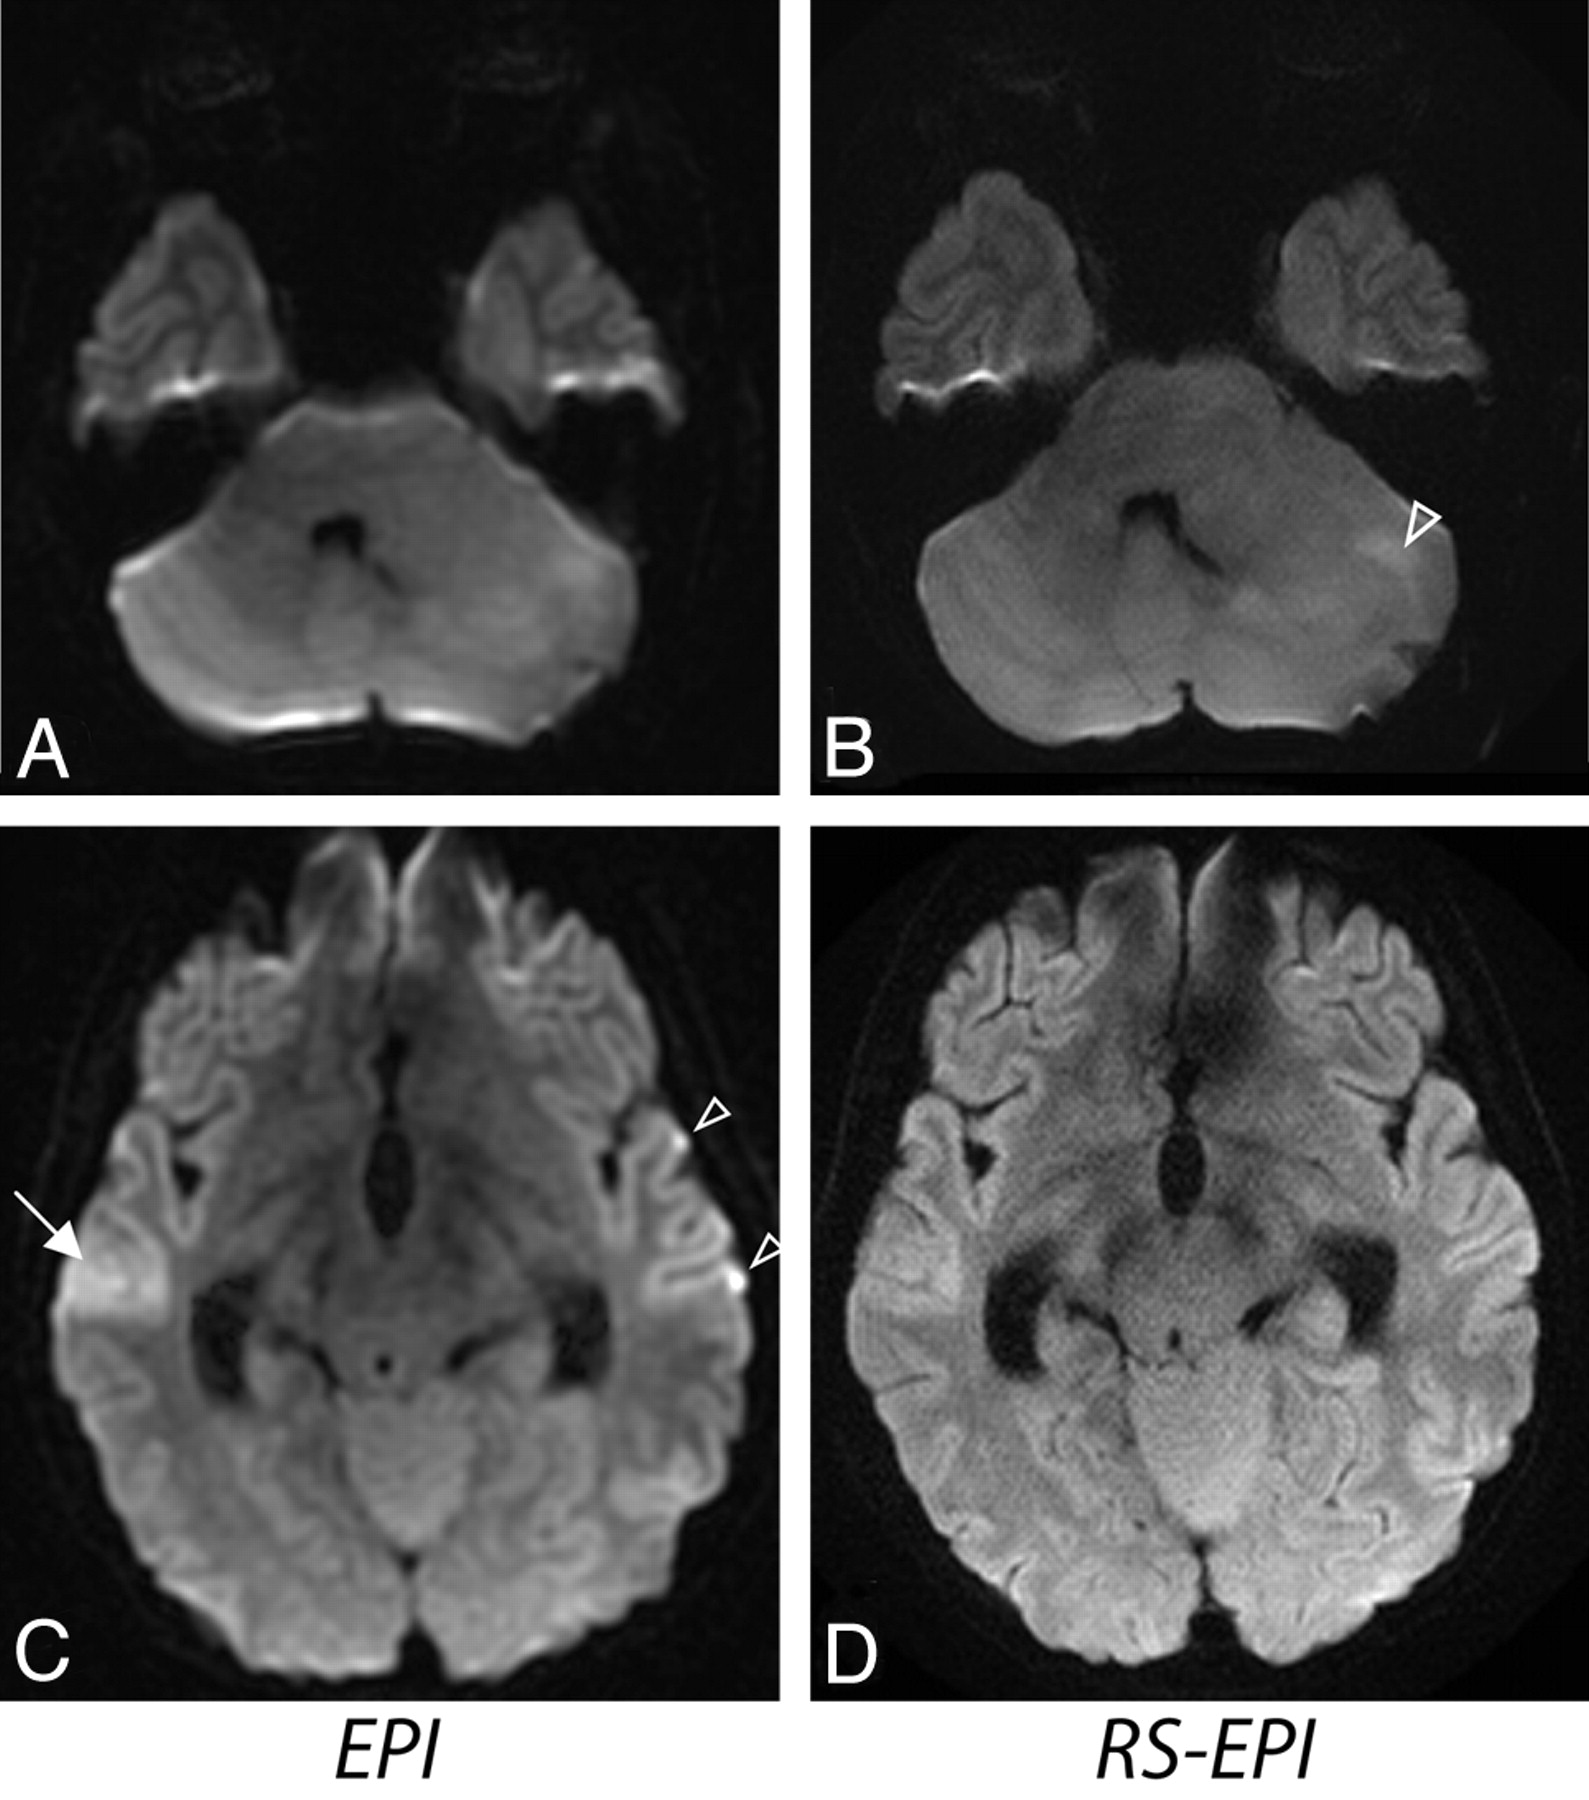

Although ASSET EPI scans had better SNR efficiency (ie, SNR per square root of the scanning time), the higher spatial resolution as well as reduced blurring and distortions on RS-EPI scans improved anatomic details at the cortical-subcortical levels, brain stem, temporal and inferior frontal lobes, skull base, nasoethmoid region in interior cranial fosa, the cranial nerves, and the orbits. Exquisite orbital detail was delineated in all 35 RS-EPI scans. Figure 9 shows side-by-side comparisons between ASSET EPI (top) and RS-EPI (bottom) DWIs in 2 patients and highlights these findings. Figure 9A shows a patient with a small subdural empyema in the middle cranial fossa, which was equivocal on conventional ASSET EPI, mostly because of poor resolution and profound signal intensity loss along the orbits. On RS-EPI, orbital details such as the optic nerve and medial rectus muscle were more clearly outlined compared with ASSET EPI. Also, due to less distortion, RS-EPI enabled tumor delineation more clearly, even at the anterior skull base and near air–soft tissue interfaces, such as the nasoethmoid. This illustrates a potential clinical use of RS-EPI in evaluating highly cellular pediatric tumors, such as neuroblastoma, retinoblastoma, and rhabdomyosarcoma, which have a propensity to occur in regions susceptible to distortion.

A, ASSET-accelerated (×2) diffusion-weighted single-shot EPI in 2 different subjects (a 3-year-old girl and a 10-year-old boy) and their corresponding diffusion-weighted RS-EPI scans. B, ASSET EPI scans have a better SNR, but orbital anatomy, such as the lens (curved arrows), optic nerve (arrows), sclera (arrowheads), vitreous humor (asterisk), and lacrimal glands (open arrow), are clearly better depicted on RS-EPI than on conventional ASSET-accelerated EPI scans.